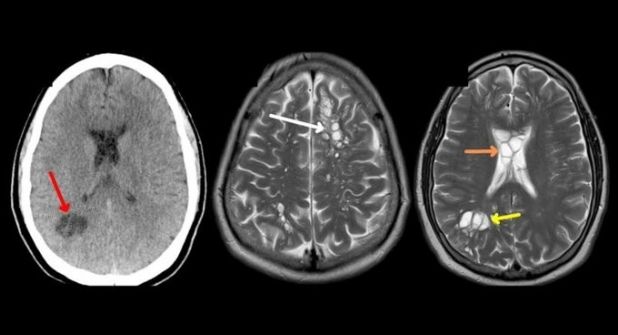

Cuando el afectado acudió a un hospital para someterse a pruebas, la tomografía computarizada reveló numerosos focos quísticos, o sea, sacos llenos de líquido en el cerebro.

Tras varias pruebas el hombre fue diagnosticado con neurocisticercosis.

Una vez en el cerebro o la médula espinal, las larvas pueden formar quistes que causan una variedad de síntomas neurológicos, como convulsiones, dolores de cabeza, confusión, alteraciones en la visión, dificultades para caminar y pérdida del conocimiento, entre otros.